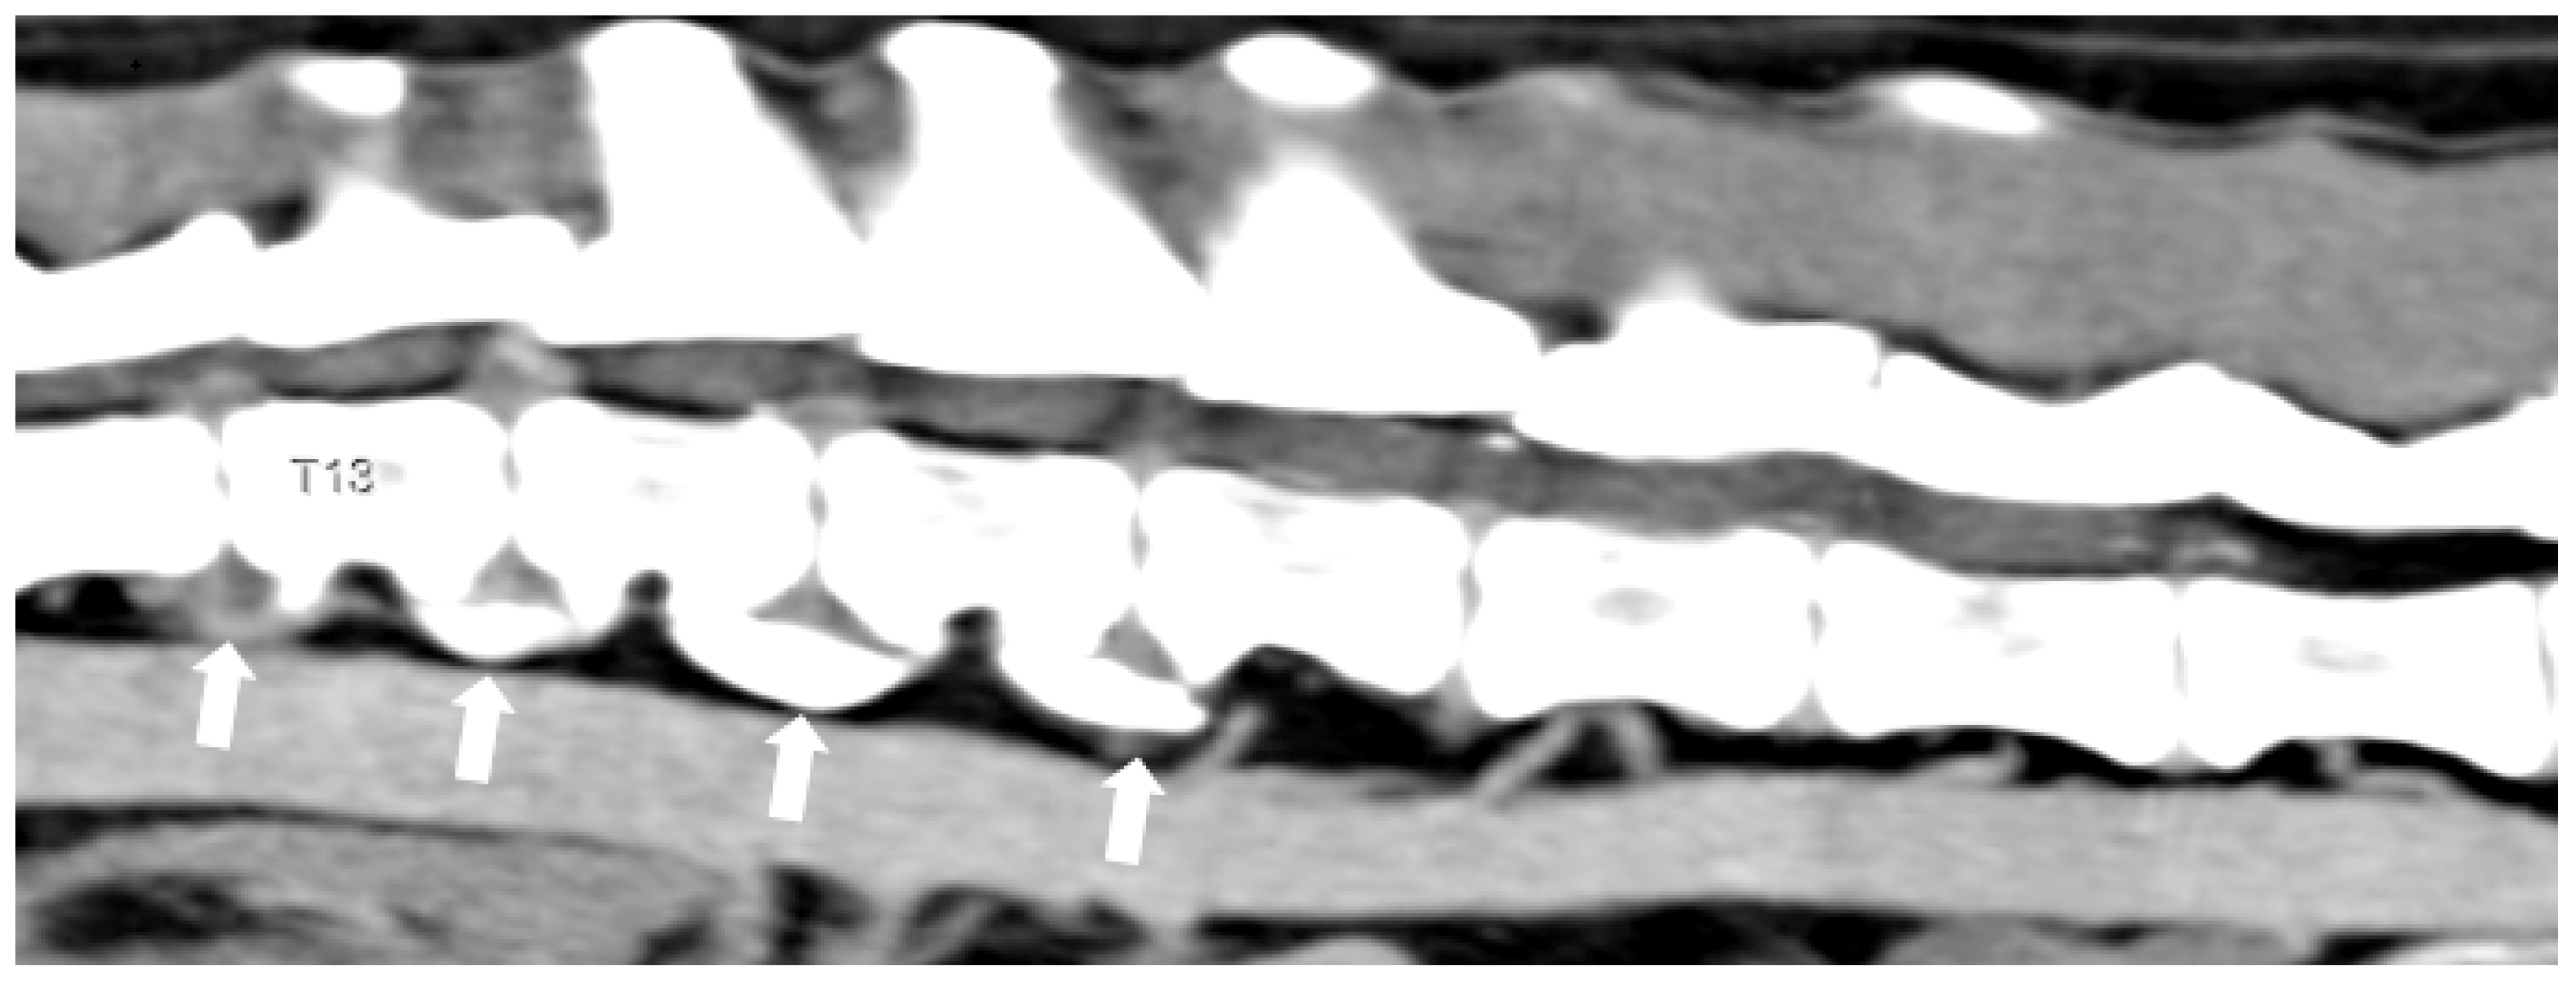

3.1. Intervertebral Disc Disease